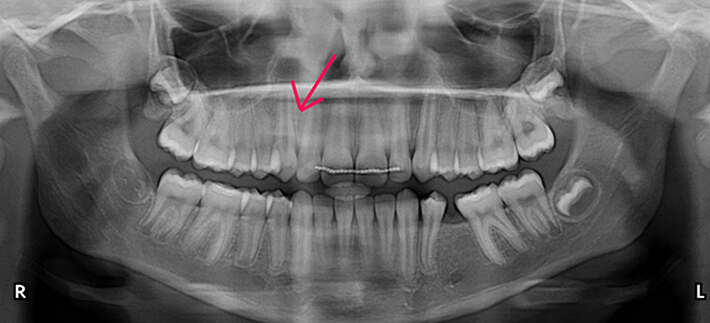

Crossbite Case

Patient presented with bilateral posterior crossbite(narrow maxilla) and underbite. Crossbite and underbite correction performed during phase I. Patient’s profile improved post-treatment.